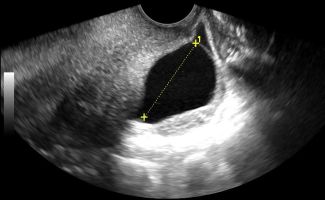

- Μήτρα: Με το Διακολπικό Υπερηχογράφημα, μπορεί να αξιολογηθεί το μυομήτριο και να εντοπιστεί η παρουσία ινομυωμάτων. Το πάχος του ενδομητρίου μπορεί να μετρηθεί με ακρίβεια, κάτι που είναι κρίσιμο τόσο για γυναίκες αναπαραγωγικής ηλικίας όσο και για γυναίκες μετά την εμμηνόπαυση ή μετά από θεραπευτικά σχήματα για νεοπλάσματα.

- Ακρίβεια: Για την ακριβή μέτρηση του πάχους του ενδομητρίου και την αξιολόγηση της ωοθηκικής δομής, το Διακολπικό Υπερηχογράφημα παρέχει σαφέστερα αποτελέσματα σε σχέση με το υπερηχογράφημα κάτω κοιλίας.